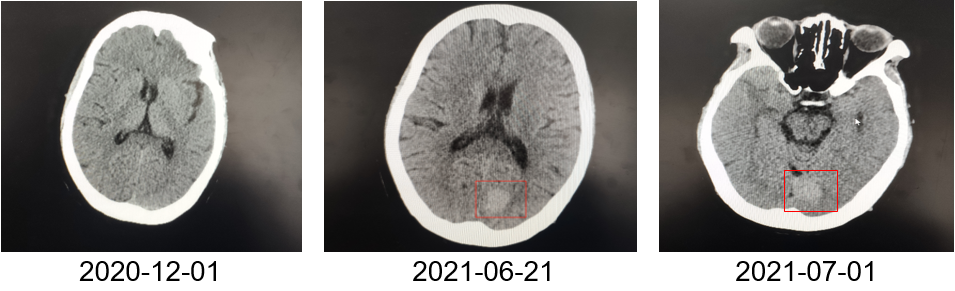

为提升肺癌前线免疫联合抗血管治疗的诊疗观念,学习与追踪肺癌领域诊疗最前沿知识,充分交流免疫/抗血管用药不良反应管理临床经验,【An例说】肺癌病例项目,征集大量临床高质量免疫联合抗血管治疗肺癌病例,并邀请全国各区域中青年及高职称医生与顶级TOP KOL互动发声!通过理念结合实践,研究结合病例,线上联动,共同促进学术由KOL/ROL向中青年医生下沉,为提升我国肺癌诊疗整体水平势在必行。免疫治疗的出现,特别是以PD-1/PD-L1为代表的免疫检查点治疗的出现,对于转移性的晚期肺癌患者而言,给患者增加了更多治疗的选择,同时,多项临床研究表明免疫治疗显著延长了患者的生存期及生活质量。为此,河北北方学院附属第一医院为您带来一例“双安疗法”用于二线治疗小细胞肺癌病例的治疗分享。 案例详情 基本情况 患者,霍xx,女,60岁。 初治时间:2020-10-16 既往史:COPD 4年,间断口服茶碱治疗,否认其他慢性病史及传染病史。否认过敏史。 个人史:无特殊 家族史:无特殊 ADL评分:90分;Khorana评分1分 入院初步检查结果 体格检查: COPD 4年,间断口服茶碱治疗,否认其他慢性病史及传染病史。否认过敏史。 个人史、婚育史、家族史无特殊。 辅助检查 血常规、肝肾功、凝血功能无明显异常。 肿瘤标志物(特异性+异常指标)。 肿瘤标志物变化趋势 NSE(神经元特异性烯醇化酶)变化趋势: NSE变化趋势 基线情况: 2020-10-16,患者无明显诱因出现咳嗽、咳痰,偶有痰中带血,伴胸闷气短4个月于我院就诊:查胸部CT:胸廓左侧塌陷,左肺上叶尖后段及下叶支气管截断,左肺下叶见软组织密度团块。右肺中叶容积小。左主支气管内见高密度影,纵隔多发肿大的淋巴结,胸膜厚,左侧少量胸膜腔积液。 浅表淋巴超声、全身骨扫描等检查提示肺外脏器未见异常。 肺部CT提示左肺占位伴阻塞性肺炎、纵隔淋巴结肿大,左侧胸腔积液。 患者遂就诊于解放军81集团军医院行支气管镜检查提示小细胞肺癌。 影像学检查 诊断结果 1.左肺小细胞肺癌(广泛期)伴胸膜转移、伴纵隔淋巴结转移 2.阻塞性肺炎 3.慢性阻塞性肺疾病 诊疗依据 (CSCO)小细胞肺癌诊疗指南2020 05治疗经过 第一阶段治疗: 胸部CT对比:较前片(2020-10-16)对比:左肺上叶复张且高密度影明显吸收;左肺占位及纵隔淋巴变化不明显,左侧胸腔积液基本吸收。 胸部CT检查对比 胸部CT对比:较前片(2020-11-26)对比:左肺占位变化不明显;纵隔部分淋巴结增大。 胸部CT检查对比 胸部CT对比:较前片(2020-12-30)对比,左肺占位明显增大,隔巴结增大,左侧胸腔新发积液,左肺上叶膨胀不全,左肺上叶新发片状高密度影。 胸部CT检查对比 胸部CT对比:较前片(2021-03-02),左肺占位性病变较前增大,纵膈肿木淋巴结较前增大。 胸部CT检查对比 胸部CT对比:较前片(2021-04-04)左肺中心型肺Ca伴左肺不张,较前增大。右肺中叶不张。纵隔多发肿大融合淋巴结,部分包绕上腔静脉,较前增大。心包少量积液、主肺动脉干增粗。左侧胸腔积液(±)。 胸部CT检查对比 头颅CT对比:2021-06-21头颅CT:考虑左枕叶、右颞叶转移瘤。尾状叶头密度增高。 头颅CT检查对比 腹部CT:较前片(2021-04-04)左肾上腺增粗,考虑转移瘤? 腹部CT检查对比 第二阶段治疗:免疫+安罗替尼。ADL评分:70分;Khorana评分3分。 胸部CT对比:对比前片(2021-06-21),左肺占位减小,纵隔部分淋巴结减小,胸腔积液吸收。 胸部CT检查对比 头颅CT对比:对比前片(2021-06-21):颅内占位变化不著。 头颅CT检查对比 胸部CT对比:对比前片(2021-07-27):左肺占位减小,纵隔部分淋巴结减小;左肺上叶片状高密度影略显吸收。 胸部CT检查对比 胸部CT对比:对比前片(2021-8-23):左肺占位及纵隔淋巴结有所减小。 胸部CT检查对比 胸部CT对比:对比前片(2021-10-29):左肺占位及纵隔淋巴结变化不著。 胸部CT检查对比 头颅CT对比:较前片(2021-07-01)对比:左枕叶、右颞叶占位明显减小。 头颅CT检查对比 胸部CT对比:对比前片(2021-11-30):左肺占位及纵隔淋巴结变化不著,腹部较前变化不著。 胸部CT检查对比 目前情况:患者神清,精神尚可,无咳嗽咳痰,偶有喘憋气短,饮食睡眠尚可,二便正常。 面部及双手皮疹样改变。 目前诊断: 1. 左肺小细胞肺癌(广泛期)伴胸膜转移、伴纵隔淋巴结转移、伴脑转移、伴肾上腺转移 2. 慢性阻塞性肺疾病 3. 下肢静脉血栓形成 4. 低钠血症 ADL评分:80分;Khorana评分2分 06病程回顾 专家点评 该病例,女性,无吸烟史,既往自2014年开始反复因咳嗽、咳痰、咯血于我院门诊或住院治疗,诊断为右中叶、双下肺基底段支气管扩张伴感染。2020年10月再次因咳嗽、咳痰、咯血行肺CT检查,检查结果示:支气管扩张、左下肺占位。后经支气管镜检查左下肺癌,病理为小细胞癌。结合肺CT:纵隔淋巴结肿大,左侧胸腔积液;临床诊断为:原发性支气管肺癌(左下广泛期小细胞肺癌)。PS评分1分,依据2020年CSCO小细胞肺癌指南Ⅰ级推荐选择化疗+免疫治疗,化疗方案:CE/EP,IC/IP,免疫治疗:atezolizumab。本病例中,患者因经济条件所限,未使用atezolizumab,化疗采用CE\EP\ZP一线及二线LE(共计7疗程),肺部病灶增大,左肺完全不张,脑转移,肾上腺转移,PS评分3分。再次依据CSCO指南,行颅脑放疗,采用PD-1(卡瑞丽珠单抗)+EP+安罗替尼(口服小分子多靶点抗血管生成药物)2个疗程后,肺部病灶明显缩小,颅内病灶消失,评效为PR;后因卡瑞丽珠单抗副作用:反应性皮肤毛细血管增生症(RCCEP)及手部皮肤皲裂,改换为派安普利单抗+EP+安罗替尼治疗,直至目前。左肺完全复张,病情明显改善,PS评分降至2分。 该患者全程治疗过程分析,单纯化疗疗效不显著,PD-1联合抗血管生成靶向药物后,使得患者病情控制,生存带来了希望。“双安”治疗方案副作用小,对PS评分高的患者也适用。派安普利单抗是唯一采用IgG1亚型且经FC段改造的新型PD-1单抗,副作用较国产其他IgG4亚型 PD-I更小;安罗替尼为口服小分子多靶点络氨酸酶抑制剂,靶点更加全面,疗效更优。采用“双安”治疗广泛期小细胞肺癌,本例虽为个例,但为临床医生提供了可践行的治疗方向,也期待着更多临床研究数据的公布,为小细胞肺癌的治疗提供强有力的治疗依据。 病例分享 王布 教授 河北北方学院附属第一医院呼吸科副主任医师,医学硕士 河北省中西医结合睡眠专业会委员 张家口市抗癌协会肺癌专业委员会委员 世界中医药学会联合会整合肿瘤专业委员会委员 在《Translational Cancer Research》、《Journal of biological regulators &homeostaticagents》、《中国临床药理学》、《中华结核与呼吸杂志》等杂志上发表学术论文10余篇,其中《川芎嗪联合顺铂影响Lewis肺癌小鼠移植瘤生长及微血管生成的研究》论文在2015年中国药学大会暨第十五届中国药师周上报告交流 荣获河北省科技进步三等奖1项,河北省医学会科技奖一等奖1项 目前以第一主研人主持河北省科技厅课题1项,市厅级课题2项 以第二主研人主持张家口市财政厅支持课题1项;河北省政府资助专科能力建设和专科带头人培养课题1项 获“河北省抗击新冠肺炎先进个人”、“河北省优秀共产党员”、“河北省冀青之星”、张家口市“最美科技工作者”,“张家口市抗击新冠肺炎先进个人”、“张家口市优秀共产党员”等荣誉称号。 专家点评 支学军 教授 河北北方附属第一医院主任医师 教授,河北北方学院硕士研究生导师 任河北省医学会内科学分会委员 张家口市医学会呼吸分会常务委员兼秘书 张家口市抗癌协会理事会理事 张家口市抗癌协会肿瘤临床化疗专业委员会常务委员 张家口市抗癌协会抗癌药物专业委员会常务委员等职务 从事呼吸科工作30余年,擅长肺部感染性疾病、肺癌、肺结核等疾病的诊治。